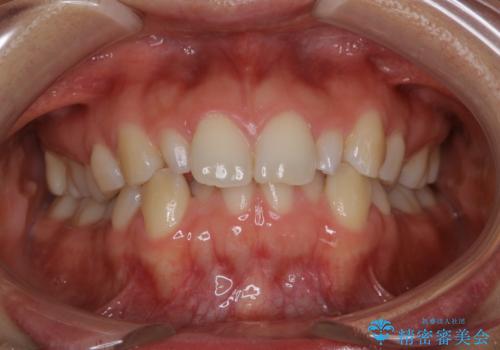

- 上の前歯が大きい事と下の前歯のがたつきを気にされてご相談にいらした方です。上の2番目の歯が矮小歯であったため、矯正治療にて歯のスペースを作った後、矮小歯には被せ物をして前歯のバランスを整えました。